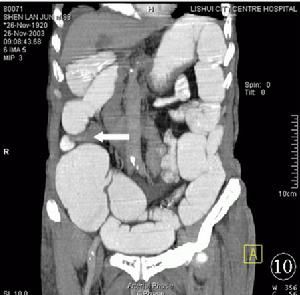

粘連性腸梗阻

急性粘連性腸梗阻主要是小腸機械性腸梗阻的表現,

病人多有腹腔手術、創傷或感染的病史,以往有慢性腸梗阻症狀和多次急性發作者多為廣泛粘連引起的梗阻;長期無症狀,突然出現急性梗阻症狀,腹痛較重,出現腹部局部壓痛,甚至腹肌緊張者,即應考慮是粘連帶等引起的絞窄性腸梗阻。 手術後近期發生的粘連性腸梗阻應與手術後腸麻痹恢復期的腸蠕動功能失調相鑑別,後者多發生在手術後3—4日,當自肛門排氣排便後,症狀便自行消失。治療